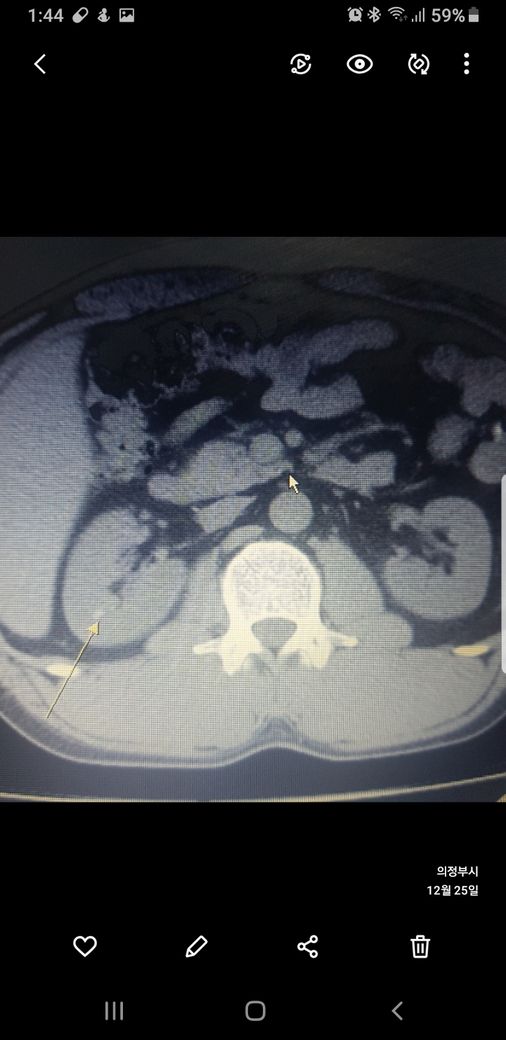

복부ct 작년 11월 , 올해 12월 촬영분입니다.

우측신장에 작년에는 1.7cm 물혹이 올해는 같은곳에 1.2cm 출혈성낭종이라는데

사진 1~4번째 는 작년

둘다 같은 병변이고 비조영증강에서 약간의 고음영 소견이 있어 출혈성 낭종이 의심됩니다.

신장의 낭성병변의 분류에서 1, 2, 2F, 3, 4이렇게 나뉘는데, 2에 해당되는 소견입니다.